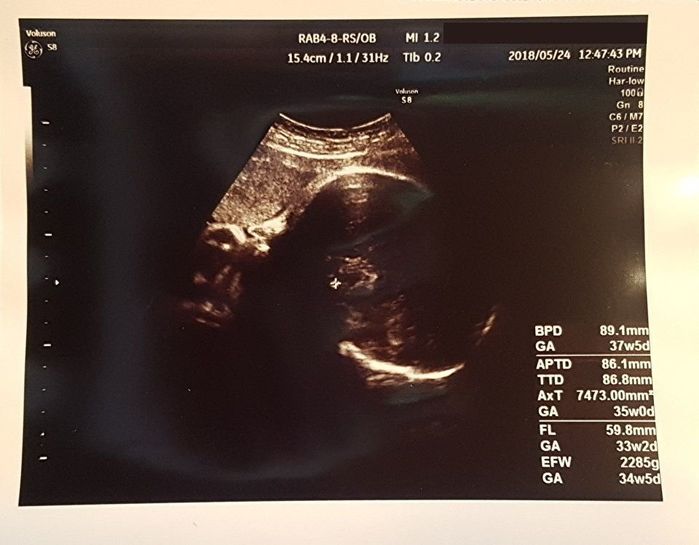

妊娠37週目 産院決定。体調も問題なし!

自然豊かなところでのびのびと子どもを育てることを夢見ていた私。とあるご縁で田舎の家を借りることができ、仕事を辞めて妊娠中2度目の引越しをしました。この時の推定体重は2285g。産院も2度目の転院です。

まずは血液検査を受け、不規則抗体の結果は陰性でした。抗体が増えていないため出産はNICUのある病院でなくても大丈夫と、先生から太鼓判をいただきました。